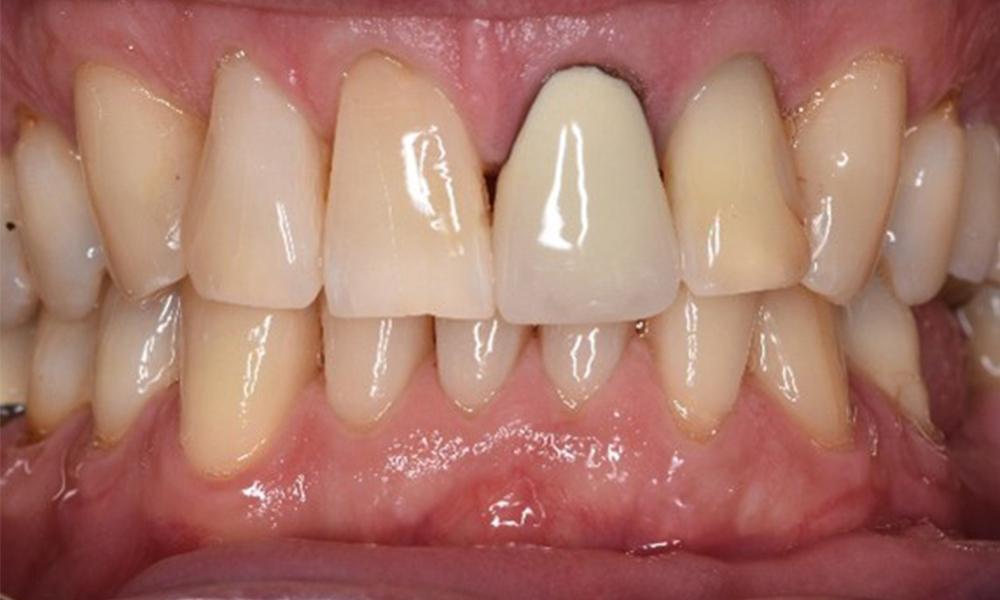

The healthy patient with pre-existing periodontal disease & peri-implantitis

A 52-year-old patient presents at a preventive care session. The patient has no systemic disease and is not taking any medication. He has had various dental treatments and also has two active carious lesions. In addition, the patient has four implants (2nd, 3rd and 4th quadrants). He is revealed to have early periodontal disease (stage IV, grade B). His periodontal condition is stable; a probing depth of Probing depths (ST) of 5 mm is only evident at the implant in region 36. Gingivitis is also identified. more